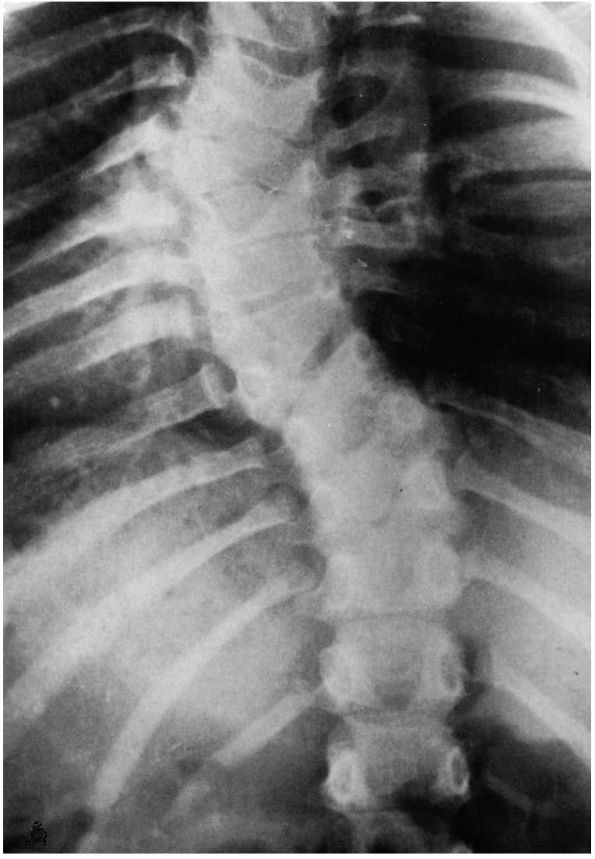

FIGURE 16-8. (A) Progressive type of infantile idiopathic scoliosis, early radiograph. Curve measures 60°. (B) Late radiograph showing marked increase of primary curve and developing secondary curves. (C) Resolving type, early radiograph. Curve measures 29°. No secondary curve. (D) Resolving type, later radiograph. Curve reduced to zero. (Courtesy of Dr. J. I. P. James)

Compensatory curves are not common in patients with infantile

idiopathic scoliosis. The development of a compensatory curve is a bad

prognostic sign that indicates a probable curve progression (Figure 16-8).